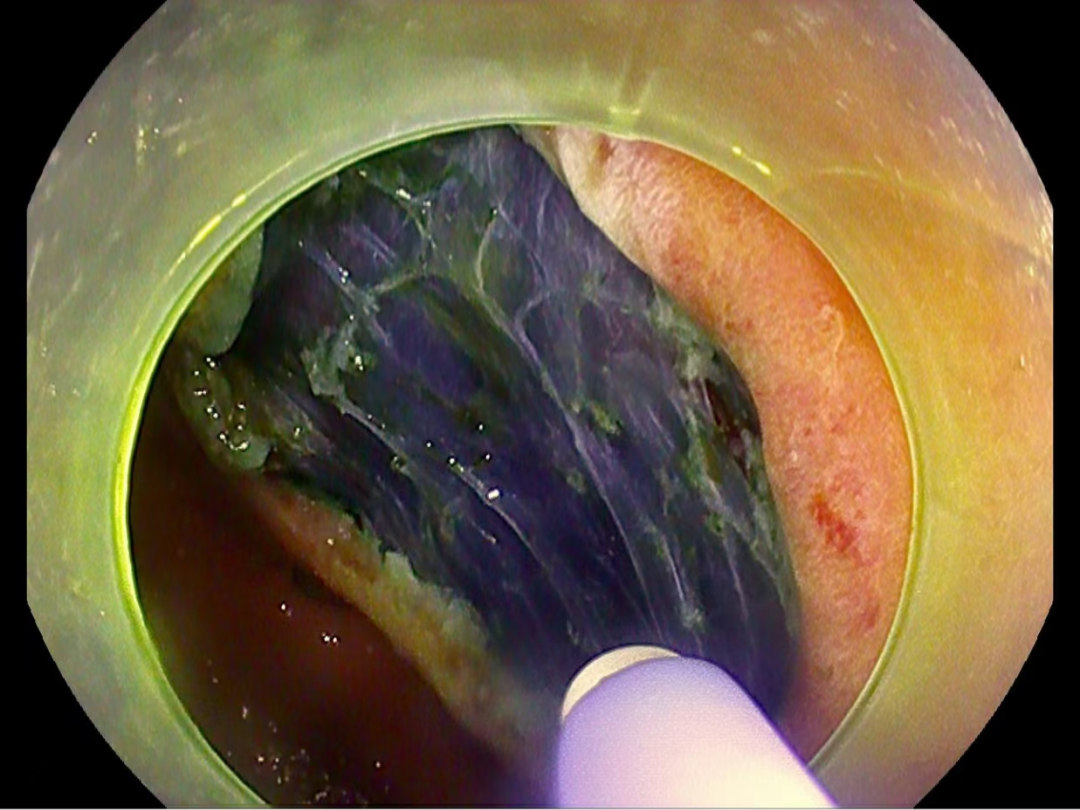

在多學(xué)科診療團隊的耐心溝通和鼓勵下,李先生同意了手術治療方案,手術采用内鏡下黏膜剝離術(ESD),這(zhè)是胃腫物病變的胃鏡下超級微創治療的手段,即在胃鏡下用微創技術將(jiāng)病變從黏膜下層完整剝離出來,能(néng)較好(hǎo)地保留胃部正常解剖結構,加上此項技術無需開(kāi)腹,術後(hòu)感染以及出血等風險較低,對(duì)患者以後(hòu)生活質量影響較小。

在蘇連明副主任醫師的帶領下,由多學(xué)科診療團隊爲李先生行氣管插管全麻下胃鏡下早期胃癌ESD術,在胃鏡下成(chéng)功將(jiāng)胃早癌病竈完整切除,術後(hòu)切除組織病理提示:胃早期癌變,切緣幹淨未見癌細胞浸潤,無需追加外科手術,胃鏡下已基本治療早期胃癌。對(duì)于這(zhè)樣(yàng)的結果,李先生激動地說(shuō):“感謝六院消化内科用先進(jìn)的技術幫助他解決了病痛,免除了外科開(kāi)刀的風險。”對(duì)于消化内科團隊的付出表示衷心的感謝,懷著(zhe)感恩且激動的心情順利出院。